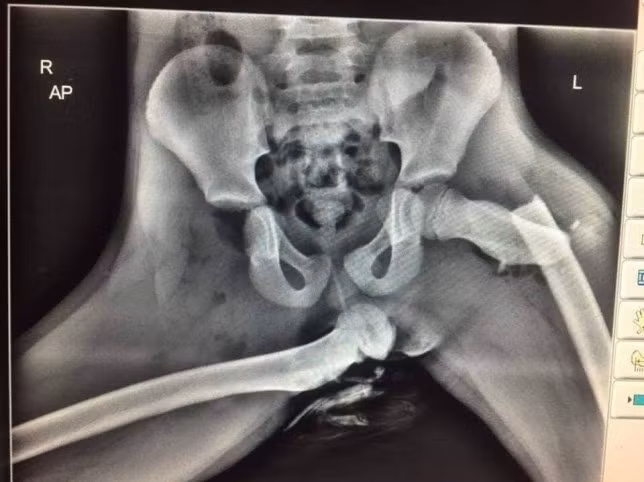

| Phim chụp X-quang một hành khách bị túi khí gây tổn thương do gác chân lên táp-lô. Ảnh: Wales News Service. |

Năm 2015, một người phụ nữ tên Audra Tatum (Georgia, Mỹ) đã bị tàn phế vĩnh viễn sau một vụ va chạm giao thông nhẹ. Nguyên nhân bởi cô đã gác chân lên táp-lô, túi khí bung hất ngược chân cô đập vào mặt, khiến mũi, mắt cá chân và xương đùi của cô bị gãy.